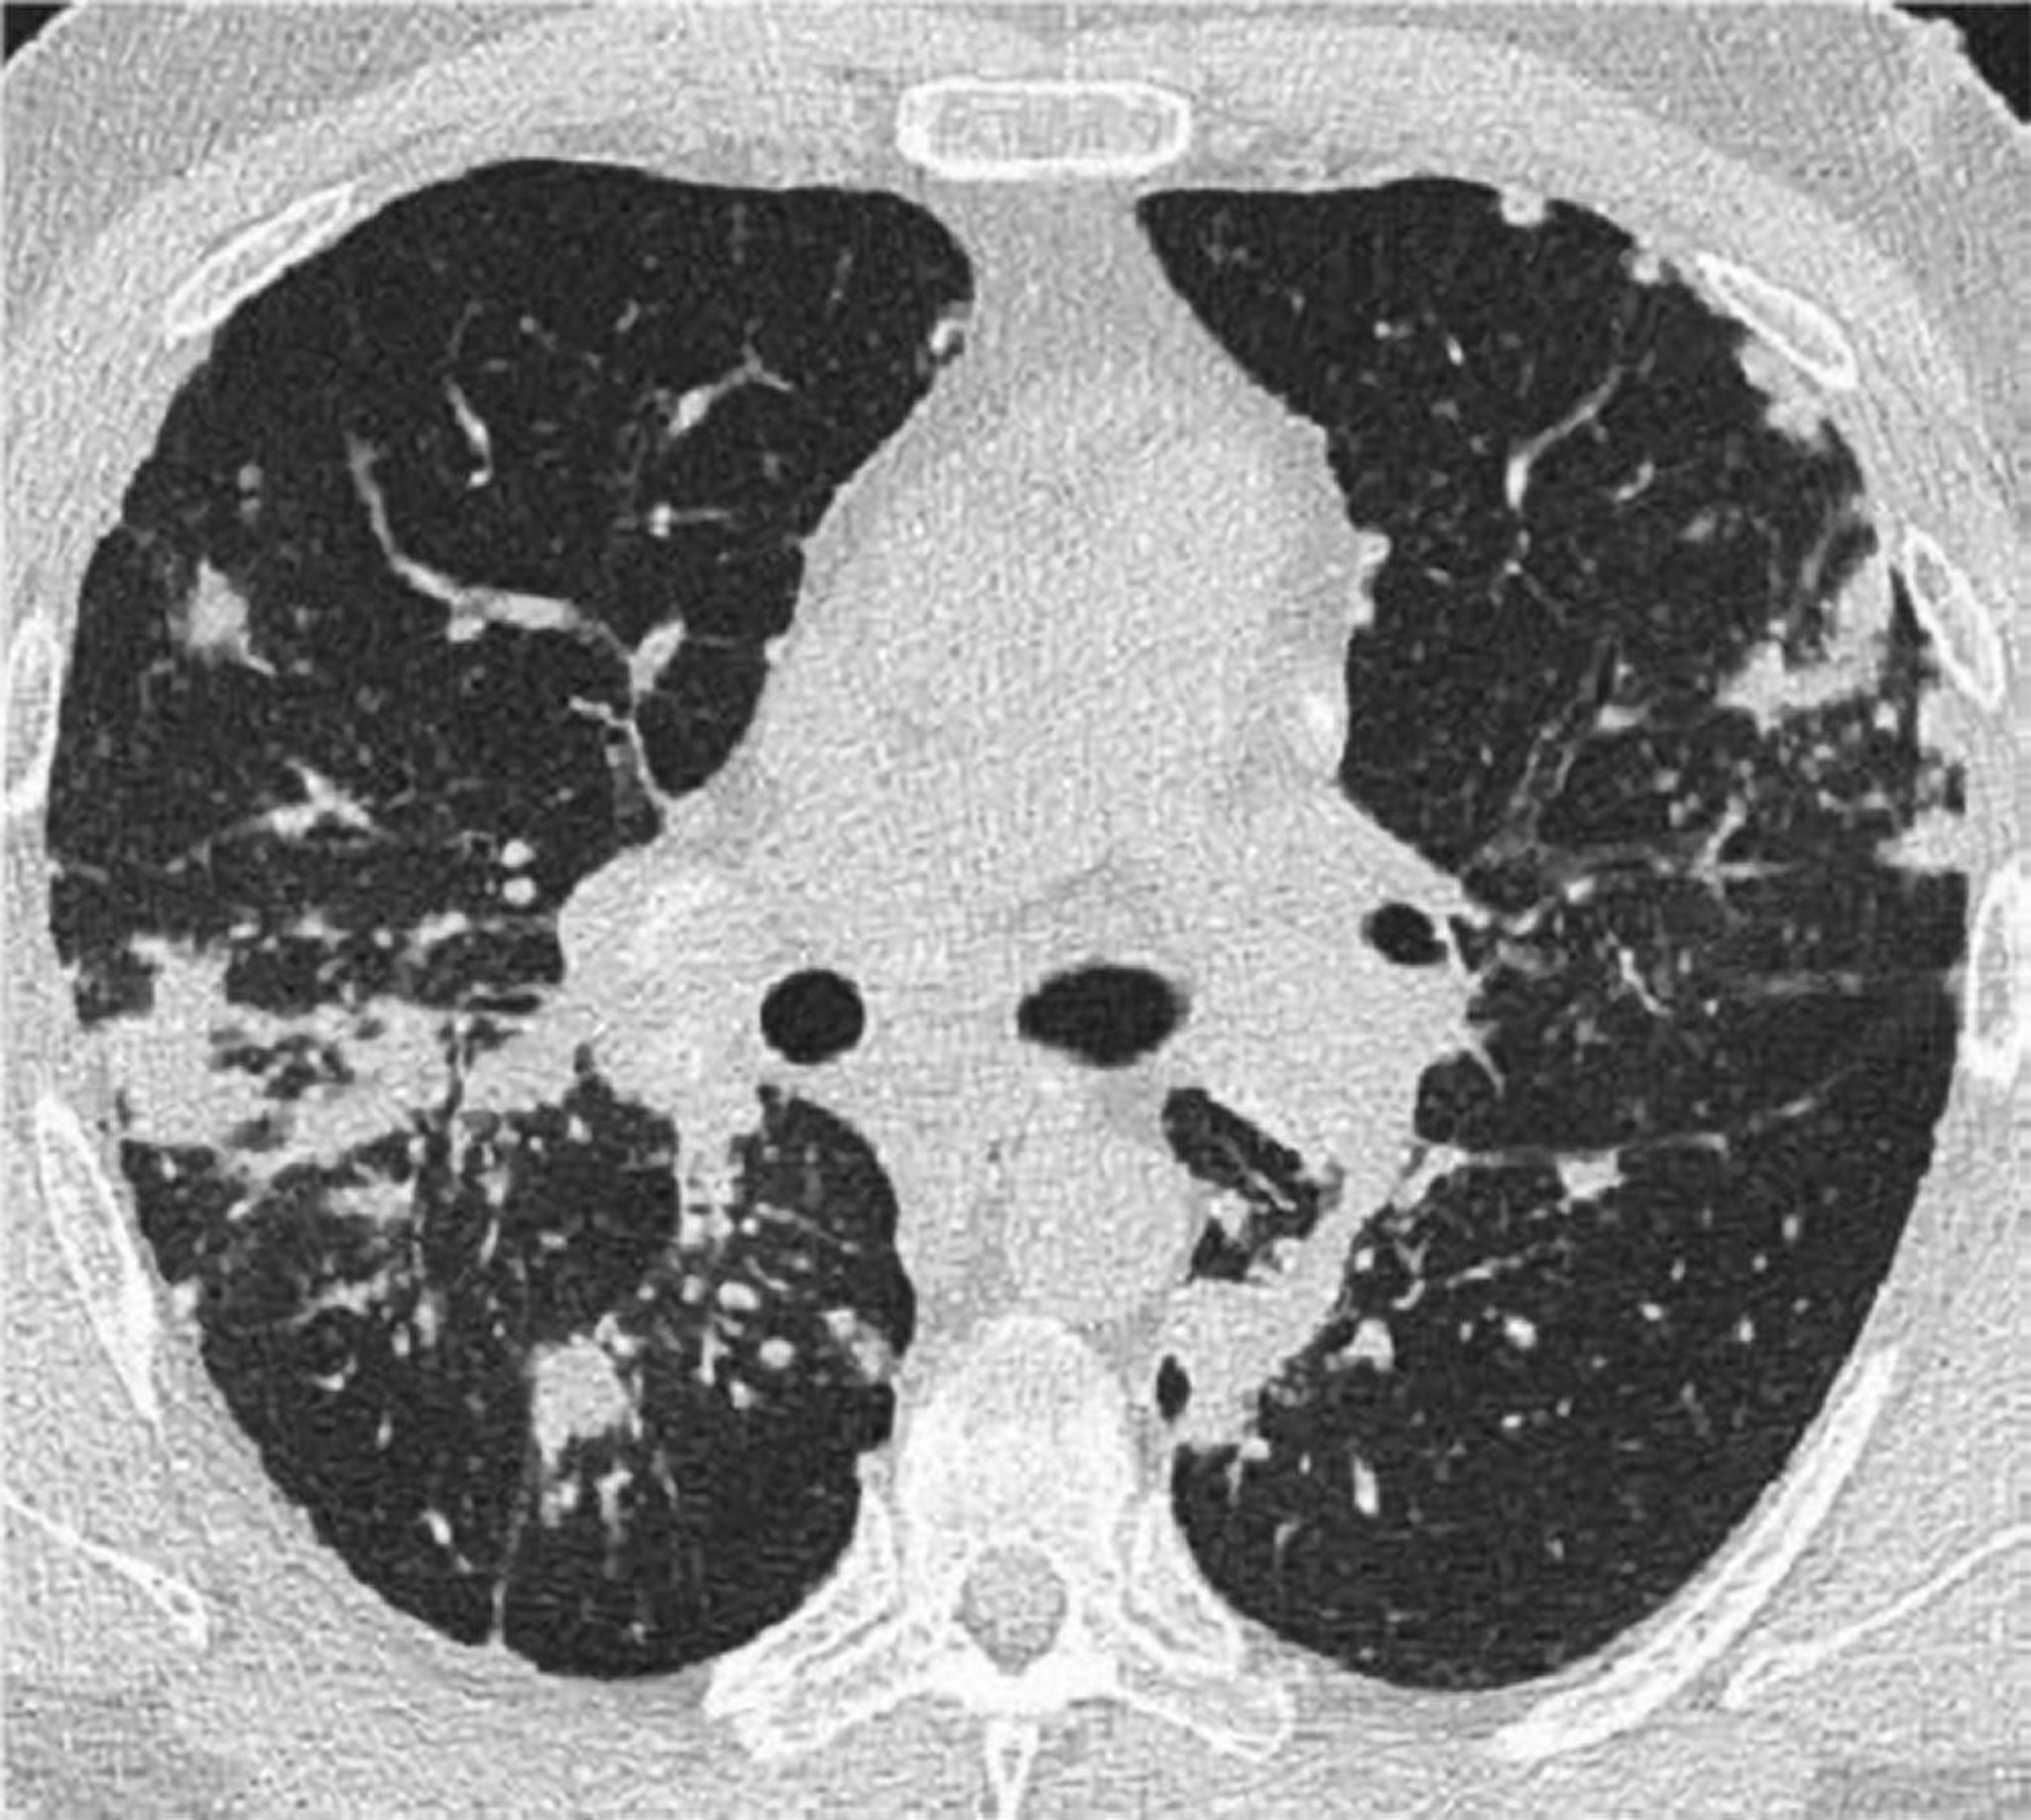

TC de tórax en la sarcoidosis pulmonar

Esta TC de alta resolución del tórax de un paciente con sarcoidosis pulmonar muestra engrosamiento de los haces broncovasculares y formación en "collar de perlas" de los tabiques interlobulillares.

Image courtesy of Birendra P. Sah, MD, FCCP.